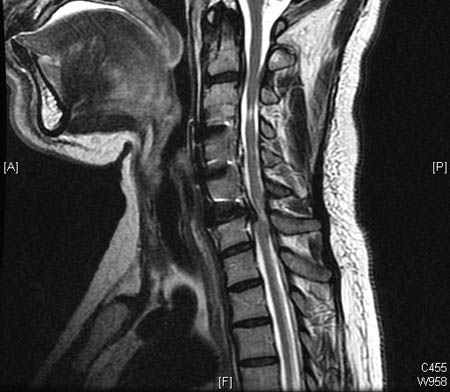

DCM usually involves severe disc and facet degeneration with changes in the alignment of the spine, such as kyphosis or spondylolisthesis, along with osteophyte formation. These lead to a significantly narrowed spinal canal and secondary spinal cord deformation.[27][Figure caption and citation for the preceding image starts]: Severe, multi-level degenerative disc disease changes but without significant spinal cord compression (i.e., neither deformation nor intrinsic T2 changes) on cervical MRI (sagittal T2)Dennis A. Turner, MA, MD [Citation ends].